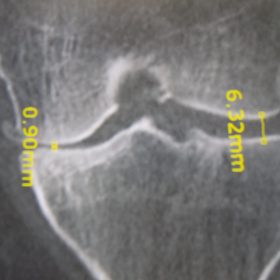

Διάγνωση- Σταδιοποίηση

Διακρίνονται σε 4 στάδια.

Στάδιο Ι. Στένωση του μεσαθριου διαστήματος

Στάδιο ΙΙ. Σκλήρυνση του υποκύμενου χόνδρου

Στάδιο ΙΙΙ. Σκλήρυνση του υπερκείμενου χόνδρου, καταστροφή του υποχόνδρινου οστούν, σχηματισμός οστεόφυτων, οίδημα αρθρώσεως και βραδυνός πόνος

Στάδιο IV. Οστική καθίζηση, καταστροφή μαλακών μορίων μυϊκών ομάδων, υπεξάρθρημα της αρθρώσεως και αλλαγή του μηχανικού άξονα